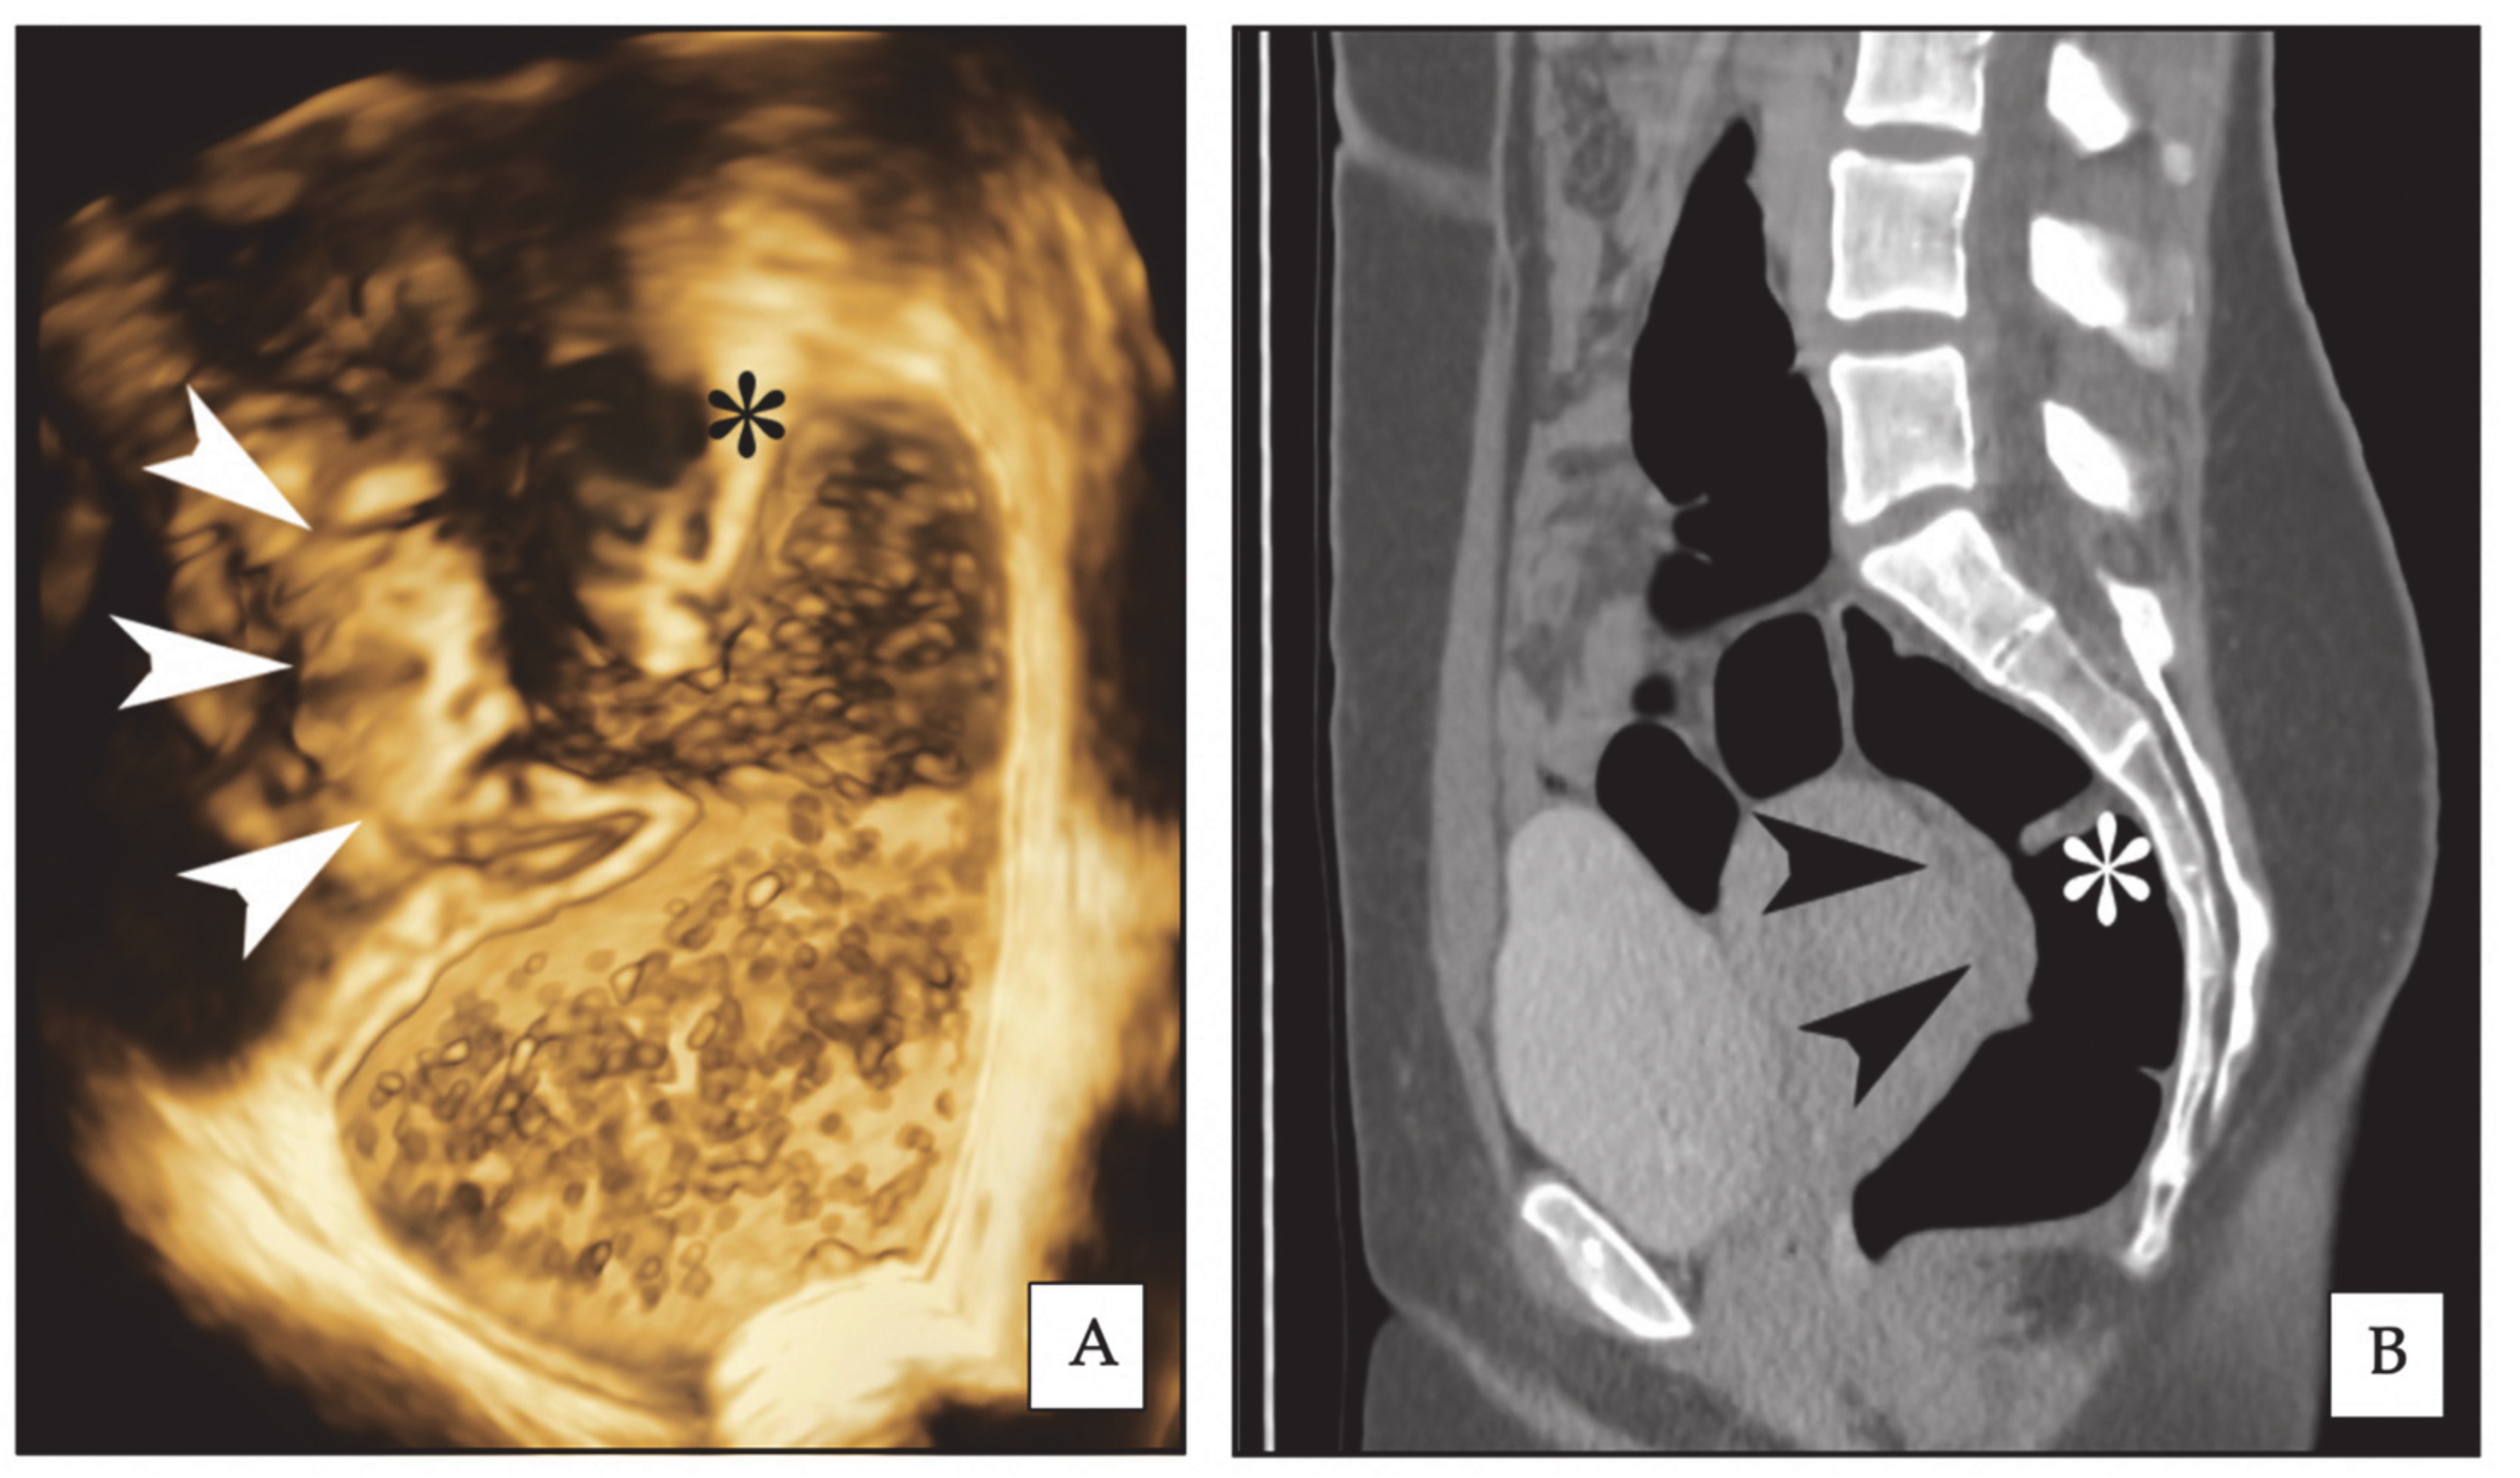

During the ultrasonographic scan, acquisitions of images by 3D rendering were made in the sagittal and coronal planes. Two specific quality enhancement tools (GE Healthcare Ultrasound, Milwaukee, WI, USA) were applied during 3D rendering: advanced Speckle Reduction Imaging (SRI), which helps heighten the visibility of lesions with high-definition contrast resolution and CrossXBeamCRITM, which improves the enhancement of tissue and border differentiation. On the 3D rendering, rectosigmoid lesions typically appear as spiculated lesions with a retracting line all around the nodule (Figure 1) [18]. Multiple acquisitions were performed to characterize the endometriotic nodules, in particular, measuring their largest diameter and their distance from the anal verge. When the volume acquisition was completed, the data file was sent via Digital Imaging and Communication in Medicine (DICOM) to a personal computer and stored in order to be analysed by the use of an appropriate software (4Dview 5.0; GE Healthcare Ultrasound, Milwaukee, WI, USA). All the acquisitions were examined by another sonographer who has performed over 1000 analysis of 3D imaging related to deep endometriosis in his life (F.B.). This sonographer was blinded to the results of the 2D-RWC-TVS. For estimating the stenosis, at least three measurements of the diameter of rectosigmoid lumen were performed above and below the nodule (mean of all measurements) in a healthy bowel; close to the nodule surface, at least one measurement every 5 mm was performed (mean of the three lower measurements).

Figure 1.

Same rectal endometriotic nodule (arrowheads) is shown in three-dimensional rectal water contrast transvaginal ultrasonography (3D-RWC-TVS) (A) and computed tomographic colonography (CTC) (B, sagittal plane). The asterisk indicates the same rectal Houston’s valve. The nodule has largest diameter of 2.6 cm.